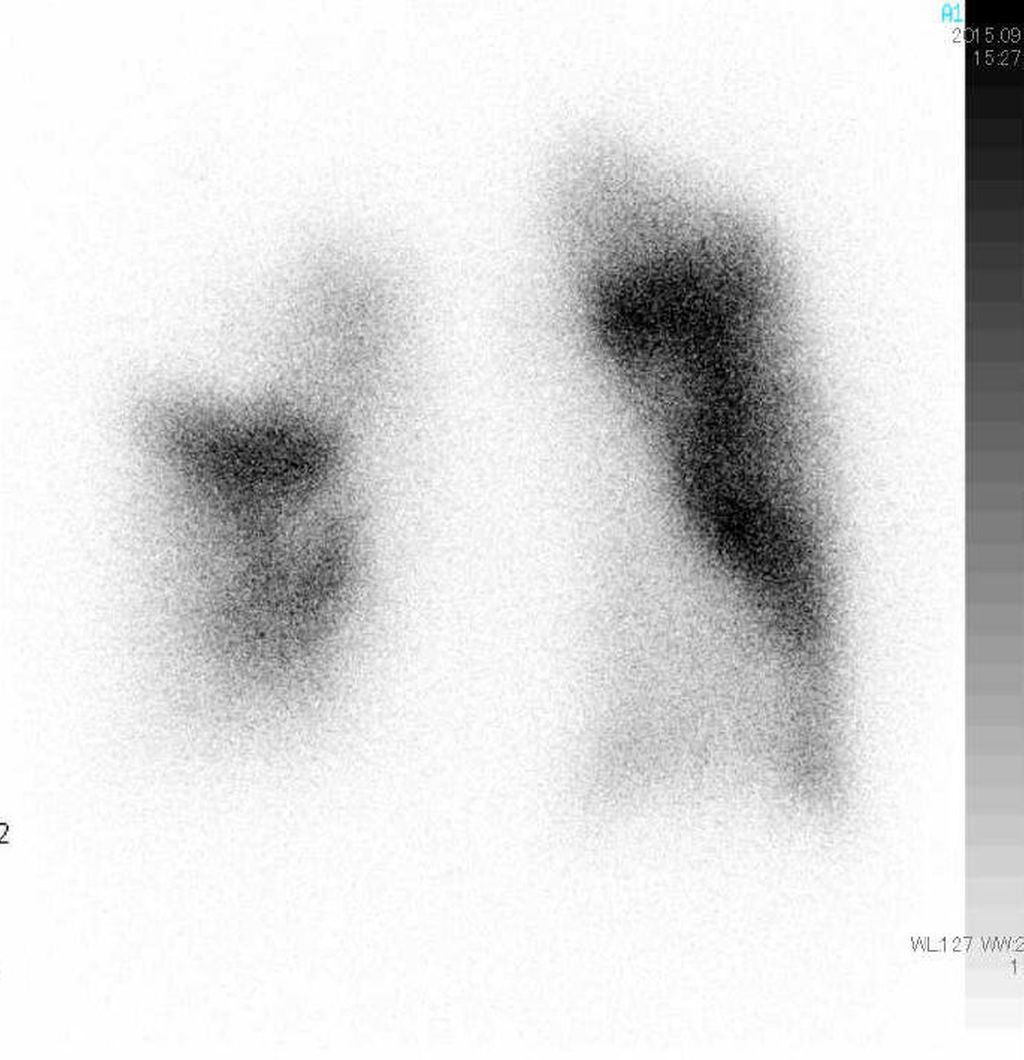

Spirometrie (Abb. 1) und DLCO (Diffusionskapazität für Kohlenmonoxid) helfen zur Erkennung von COPD, interstitiellen Lungenerkrankungen oder Hypoventilationssyndromen. Hochauflösende CT-Thoraxuntersuchungen sind unerlässlich zur Erkennung von parenchymatösen Lungenerkrankungen, Emphysem und Fibrose. Ventilations-/Perfusions-Scan (V/Q-Scan) ist empfohlen bei allen Patienten mit Verdacht auf PH zum Screening auf CTEPH, da eine hohe Sensitivität für Perfusionsdefekte besteht (Abb. 2). CT-Lungenangiografie (CTPA) liefert anatomische Details bei Verdacht auf CTEPH oder akute Lungenembolie. Die Schwäche der CTPA ist ihre schlechte Auflösung in distalen kleinen Gefäßen.

Abb. 2: Anterior-posteriores Projektions-Bild einer Perfusionsszintigraphie bei Chronisch Thromboembolischer Pulmonaler Hypertension (CTEPH). Es zeigen sich typische keilförmige Defekte. Die dazugehörige Ventilationsszintigraphie ist normal, und wird oft übersprungen. Die Perfusionsszintigraphie ist der sensitivste Screeningtest für CTEPH, beweist aber die Erkrankung nicht.